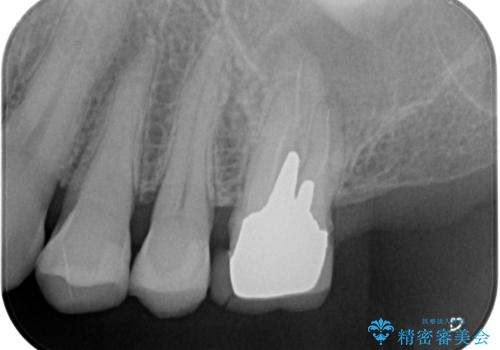

しかしながら、レントゲンやCT画像から、手前の破損したクラウンの根尖部に大きな病変が認められ、インプラント埋入部にまで病変が及んでいることから、まずは手前の根管治療を行い、病変の正体を確認した後にインプラント埋入を行うこととしました。

口があまり開かず、インプラントの埋入角度がやや斜めとなりましたが、機能的には全く問題なく治療を終えることができました。